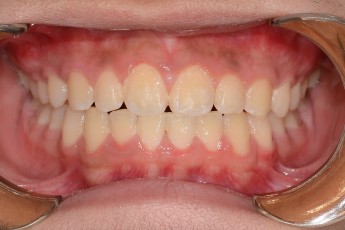

Before

After